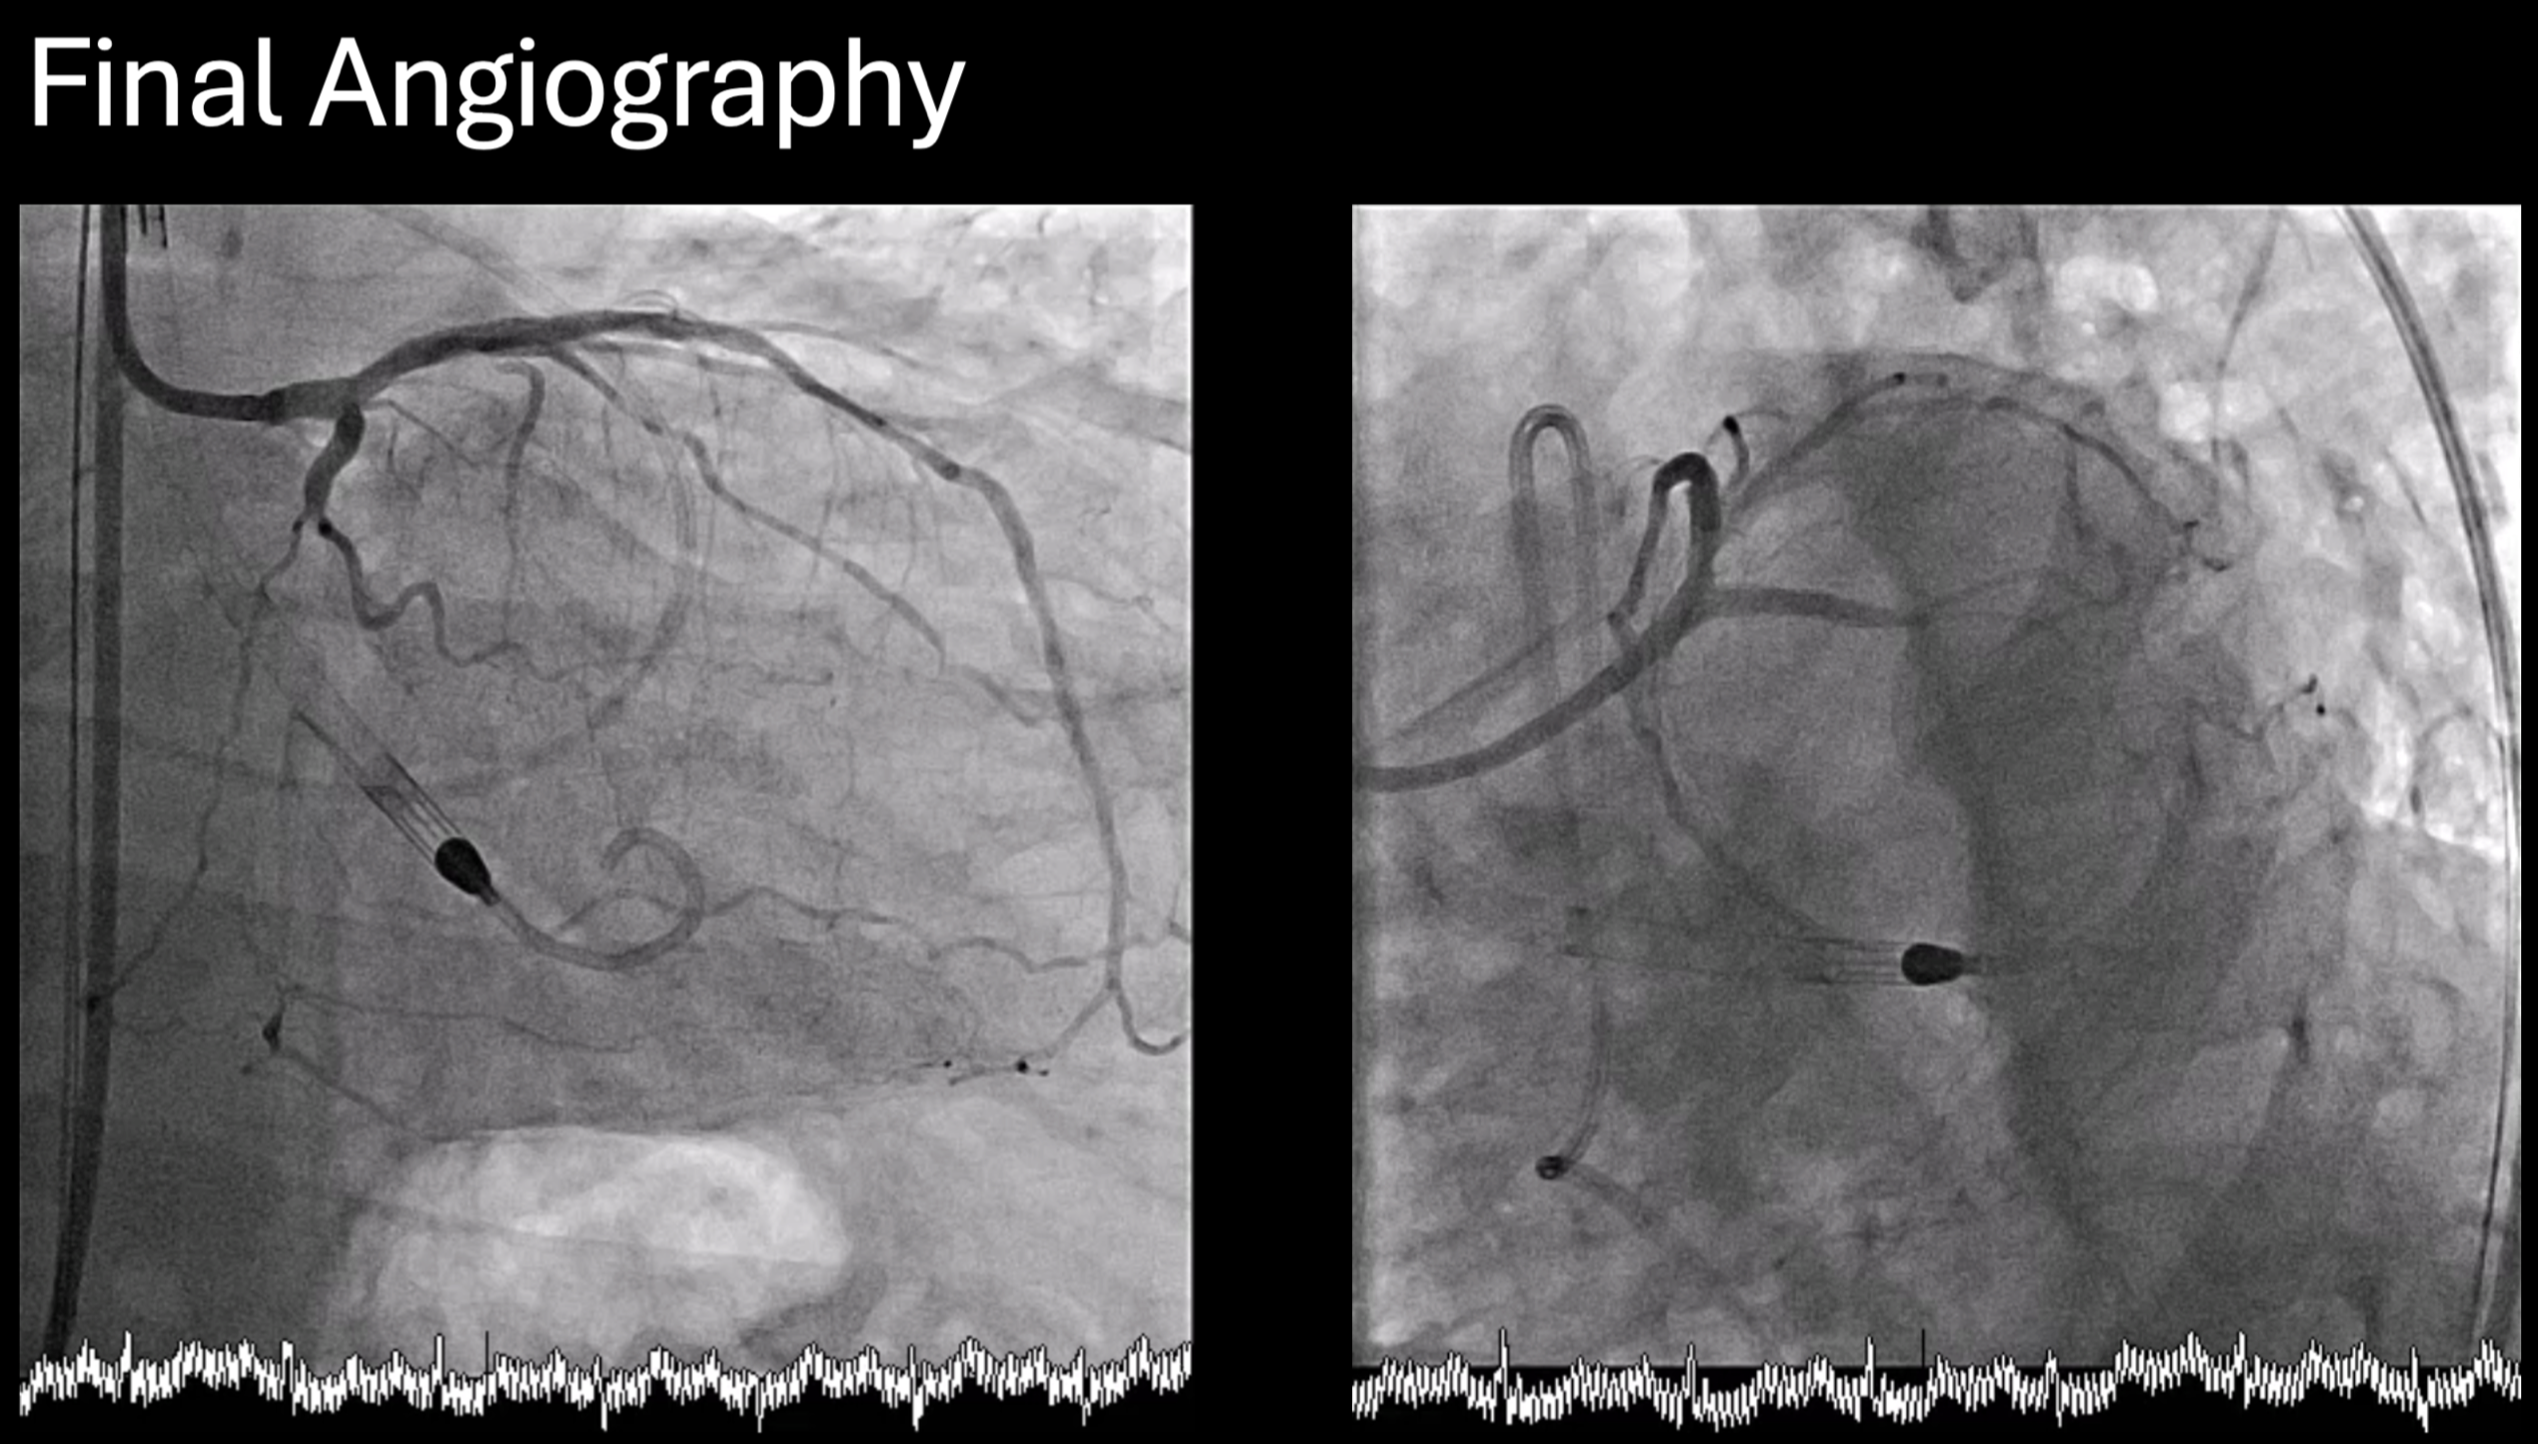

Vascular duplex was performed instead of CT for large-bore access evaluation due to acute kidney injury, revealing severe stenosis of the left common femoral artery. Despite this, an Impella CP¢ç sheath was successfully inserted using contralateral injection and fluoroscopic-guided puncture, and the device was advanced into the left ventricle uneventfully. Initial hemodynamic data from the pulmonary artery catheter showed elevated pulmonary artery wedge pressure (32 mmHg), pulmonary hypertension (68/22 mmHg, mean 43 mmHg), and a low cardiac index (1.98 L/min/m©÷) without vasopressors or inotropes. The wedge pressure decreased to 23 mmHg after Impella insertion, demonstrating effective hemodynamic support. A Medtronic 8 Fr EBU 3.5 guiding catheter with a side hole was used to engage the left coronary artery. IVUS of the LAD and LCx showed diffuse mixed calcified and fibrotic plaques with similar luminal diameters from the ostium to the proximal segments. Based on these findings, an upfront two-stent Culotte strategy was adopted. Both ostial-to-proximal LAD and LCx were pre-dilated with 3.0 mm balloons, followed by successful deployment of 3.0 ¡¿ 23 mm and 3.0 ¡¿ 28 mm drug-eluting stents to the LCx and LAD, respectively. The proximal-to-mid LAD and diagonal branch were also treated. After stent implantation, the patient was weaned smoothly from Impella, with pulmonary artery wedge pressure mildly elevated (23 mmHg after insertion and 25 mmHg post-procedure).